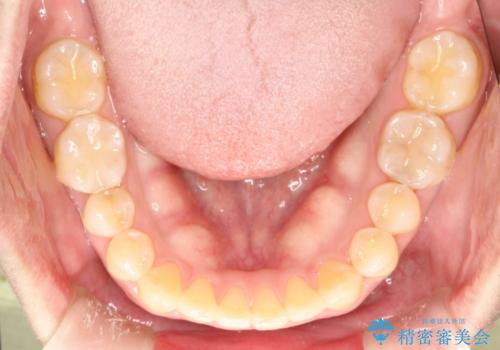

- 上顎の正中の隙間が気になるとのことで来院されました。

下の歯と歯の間をわずかに削り、スペースを作り、正中の隙間を閉じる計画としました。

装置はインビザラインにて行いました。

インビザラインで目立たずに矯正治療を行うことができました。

使用時間を守っていただけたので、比較的スムーズに矯正を終了することができました。